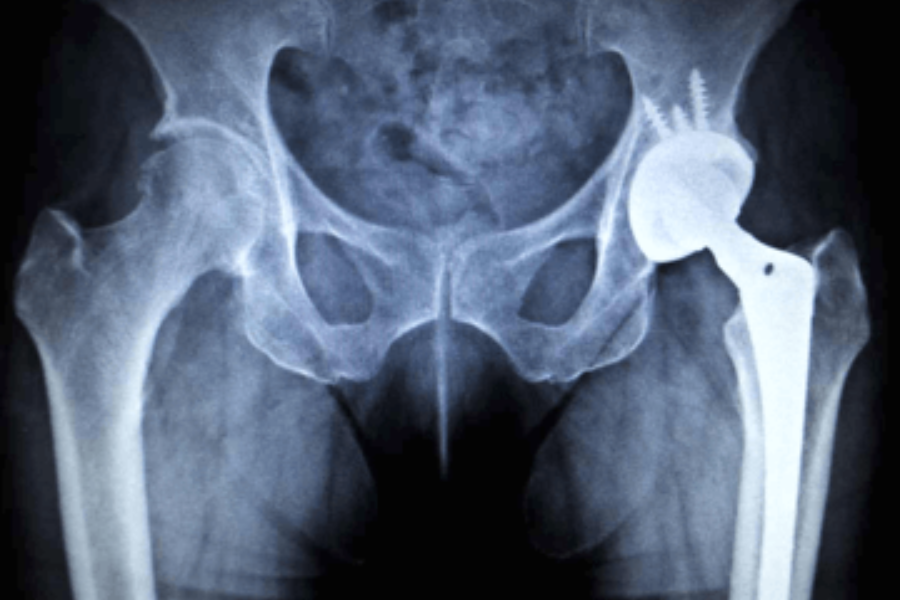

L’ artroprotesi totale di anca è un’ articolazione artificiale realizzata con speciali leghe metalliche, materiale plastico (polietilene) e/o ceramica che sostituisce i due capi articolari malati.

La protesi totale di anca è composta da una componente femorale lo stelo su cui è inserita una testina che riproduce la testa femorale, realizzata in metallo o ceramica, la quale si articola con la coppa che si fissa  all’ acetabolo, realizzata completamente in metallo o più frequentemente in metallo alla periferia ed  all’ interno in polietilene per articolarsi alla testina protesica (Fig.1). La fissazione delle due componenti protesiche all’ osso adeguatamente preparata avviene con il cemento (tecnica più antica) o a press fit (a pressione) se l’ osso è di buona qualità.